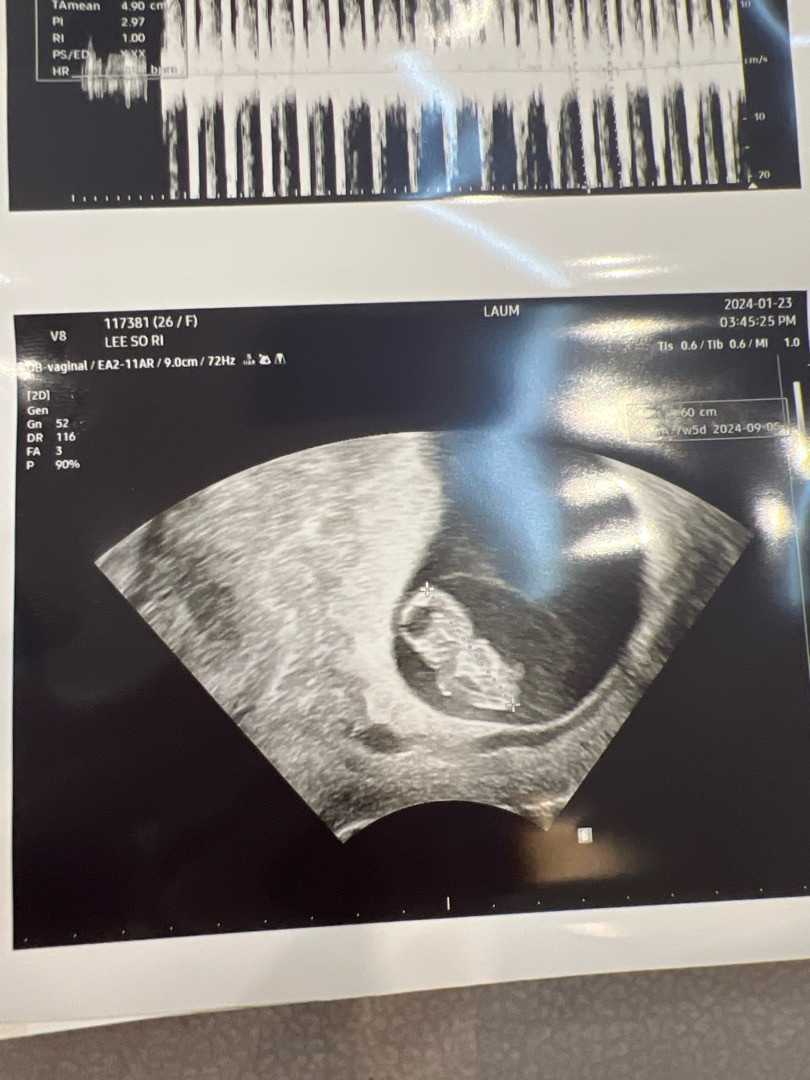

7주5일

젤리곰 봤어용😊 입덧때매 하루하루 너무 살기 힘들지만.. 진짜 귀엽네용 ㅠㅠ 7주5일이라 젤리곰은 기대 안했는데 ㅎㅎ 넘 좋아용

끼양 너무귀여워요❤️❤️어디가 머리고 몸인지 알꺼같아용 ㅋㅋㅋㅋㅋㅋ귀여운젤리 무럭무럭 자라라❤️❤️